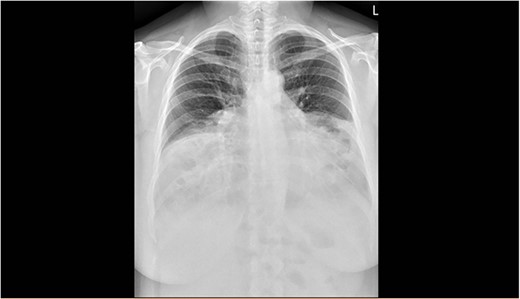

The spirometry results from her General Practitioner showed a restrictive pattern with FVC of 2.08L (55% predicted), FEV1 of 1.62L (54% predicted) and FEV1/FVC ratio of 0.78 (96% predicted). Her chest X-ray demonstrated a large hiatus or congenital hernia (Fig. 1). Subsequent computed tomography (CT) of the chest, abdomen and pelvis showed a large 88 × 48-mm defect of the anterior diaphragm consistent with MH. Hernial contents extended to the superior mediastinum and were primarily large bowel and omentum, with no intestinal obstruction (Figs 2–4).

Posterior/anterior chest X-ray showing the reduced size of both lung fields and presence of abdominal contents in the chest cavity bilaterally.